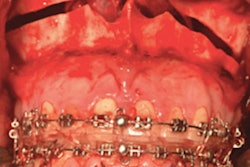

To get patients a more functional reconstruction, the team works with biomedical engineers to preplan each patient's surgery. Engineers use computed tomography scans of a patient's jaw and fibula and an intraoral scan of the person's teeth to create 3D-printed custom guides that are used to cut bones and place dental implants in the fibula bone before it is removed from the patient's leg. Also, a custom fabricated titanium plate is created to hold the transplanted bone in place.

After the implants are placed in the fibula, the damaged jawbone is removed. Then, surgeons cut and move the section of fibula into place and connect the blood vessels and nerves to the transplanted bone. The procedure, which this team of surgeons started performing in March, can take up to 15 hours, according to the release.

Following the procedure and multiple days in the hospital, a patient must wait three months for the new bone to fuse into place. Final prosthetic teeth can be placed once fusing is completed.